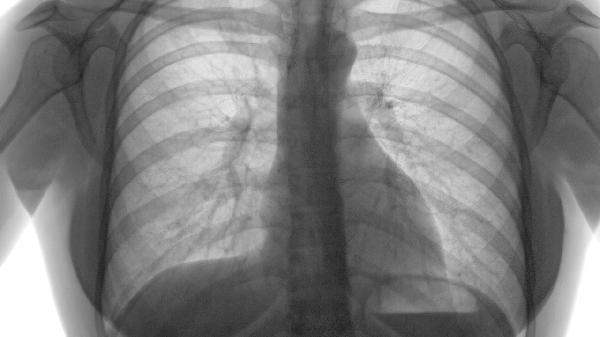

肺气肿拔罐可能有一定的辅助效果,但无法根治疾病。肺气肿是一种慢性肺部疾病,主要表现为肺泡壁破坏、肺弹性减弱和气体交换功能障碍。拔罐作为中医传统疗法,通过负压刺激皮肤和经络,可能帮助缓解症状,但不能替代现代医学的治疗手段。